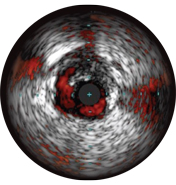

Malapposition is identified by blood behind the stent struts. ChromaFlo imaging colors blood flow red for easy recognition of malapposition and other lumen features.

• Easy assessment of stent apposition, lumen size and more by highlighting blood flow red at the touch of a button